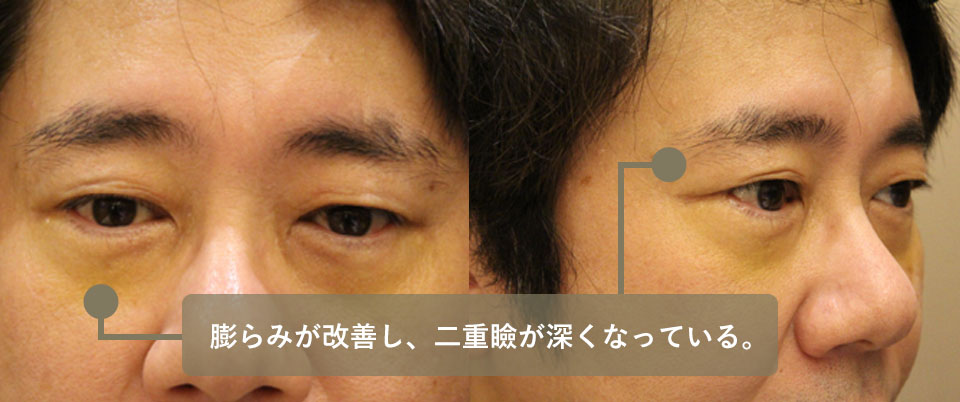

美容外科手術後の修正についてA大学病院の美容外科で皮膚からの脂肪移動術(ハムラ法)したものの改善なく有名な美容外科で結膜から脂肪切除、さらに皮膚切開からの脂肪切除、再度結膜からの脂肪切除、と計4回美容外科での手術を施行された方です。

最後にB美容外科で行った手術では瘢痕のためほんのわずかな量の脂肪(小豆大と言われたそうです)しか切除できなかったとのことでした。どうにか改善したいと悩まれて受診しました。

明らかに大きな脂肪の突出があり、下眼瞼も上眼瞼も膨らんでいました。

このためバセドウの方の減圧に準じて眼窩深部の脂肪減圧手術を行いました。

今までに数回の手術を繰り返していますので入り口は瘢痕でガチガチでしたが、思った通りその後ろ(眼窩深部)の脂肪は操作されていませんでしたので比較的簡単に切除することが出来ました。

術前後の写真を提示いたします。